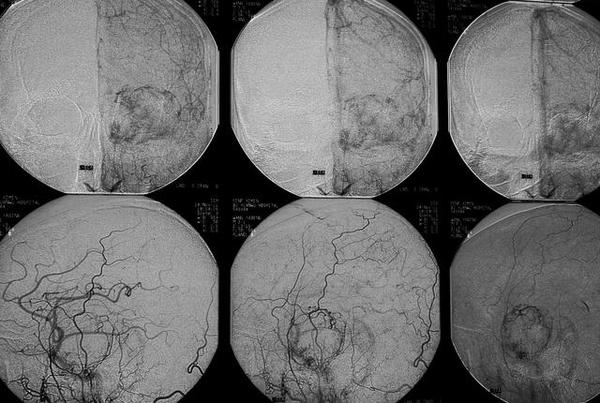

海绵窦内海绵状血管瘤行DSA检查时,多表现为海绵窦内血管显影较少的病变,常无典型的供血动脉和引流静脉,仅少数瘤体显示小斑点状染色或“池状”造影剂浓集,可见颈内动脉移位、包裹、但无狭窄征象 。海绵窦海绵状血管瘤一直是神经外科手术治疗的难点。显微手术切除是最有效的治疗方法 ,理想的手术效果是既全切肿瘤,又减少出血,同时避免损伤颈内动脉和海绵窦区的颅神经。